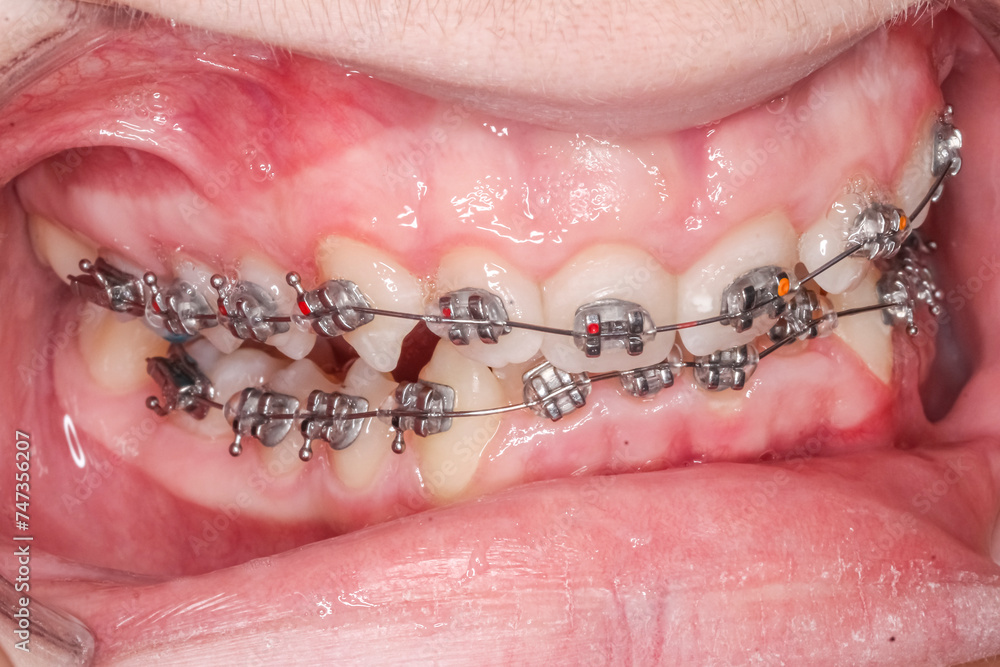

From cdieindia.com

Bite Correction With Braces Affordable & Acccurate Misaligned Teeth Causing Cheek Biting Alignment of your upper teeth will prevent you from biting your cheeks and lips. There are several different types of misaligned bites, also called malocclusions. Malocclusions are responsible for a number of different dental health symptoms people may experience due to. This can be due to a range of factors, including misalignment of the. Malocclusion is the most common reason. Misaligned Teeth Causing Cheek Biting.